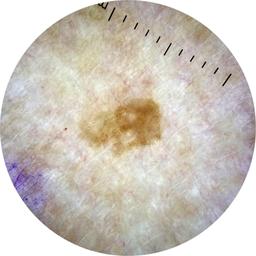

ISIC_7268078

Information

1781 x 1781

Clinical

Field Value

acquisition_day 226

age_approx 60

anatom_site_1 Trunk

anatom_site_2 Posterior trunk

anatom_site_general posterior torso

concomitant_biopsy False

diagnosis_1 Benign

diagnosis_confirm_type single image expert consensus

family_hx_mm False

image_manipulation instrument only

image_type dermoscopic

lesion_id IL_3039460

patient_id IP_4030734

personal_hx_mm True

sex female